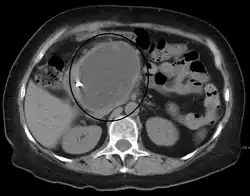

| A pancreatic pseudocyst as seen on CT | |

A pancreatic pseudocyst is a circumscribed collection of fluid rich in pancreatic enzymes, blood, and non-necrotic tissue, typically located in the lesser sac of the abdomen. Pancreatic pseudocysts are usually complications of pancreatitis,[5] although in children they frequently occur following abdominal trauma. Pancreatic pseudocysts account for approximately 75% of all pancreatic masses.[6]

- Computerized tomography[10] – this is the gold standard for initial assessment and follow-up.